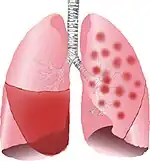

![]() | |

| Typical distribution of lobar pneumonia (left in image) and bronchopneumonia (right in image) | |